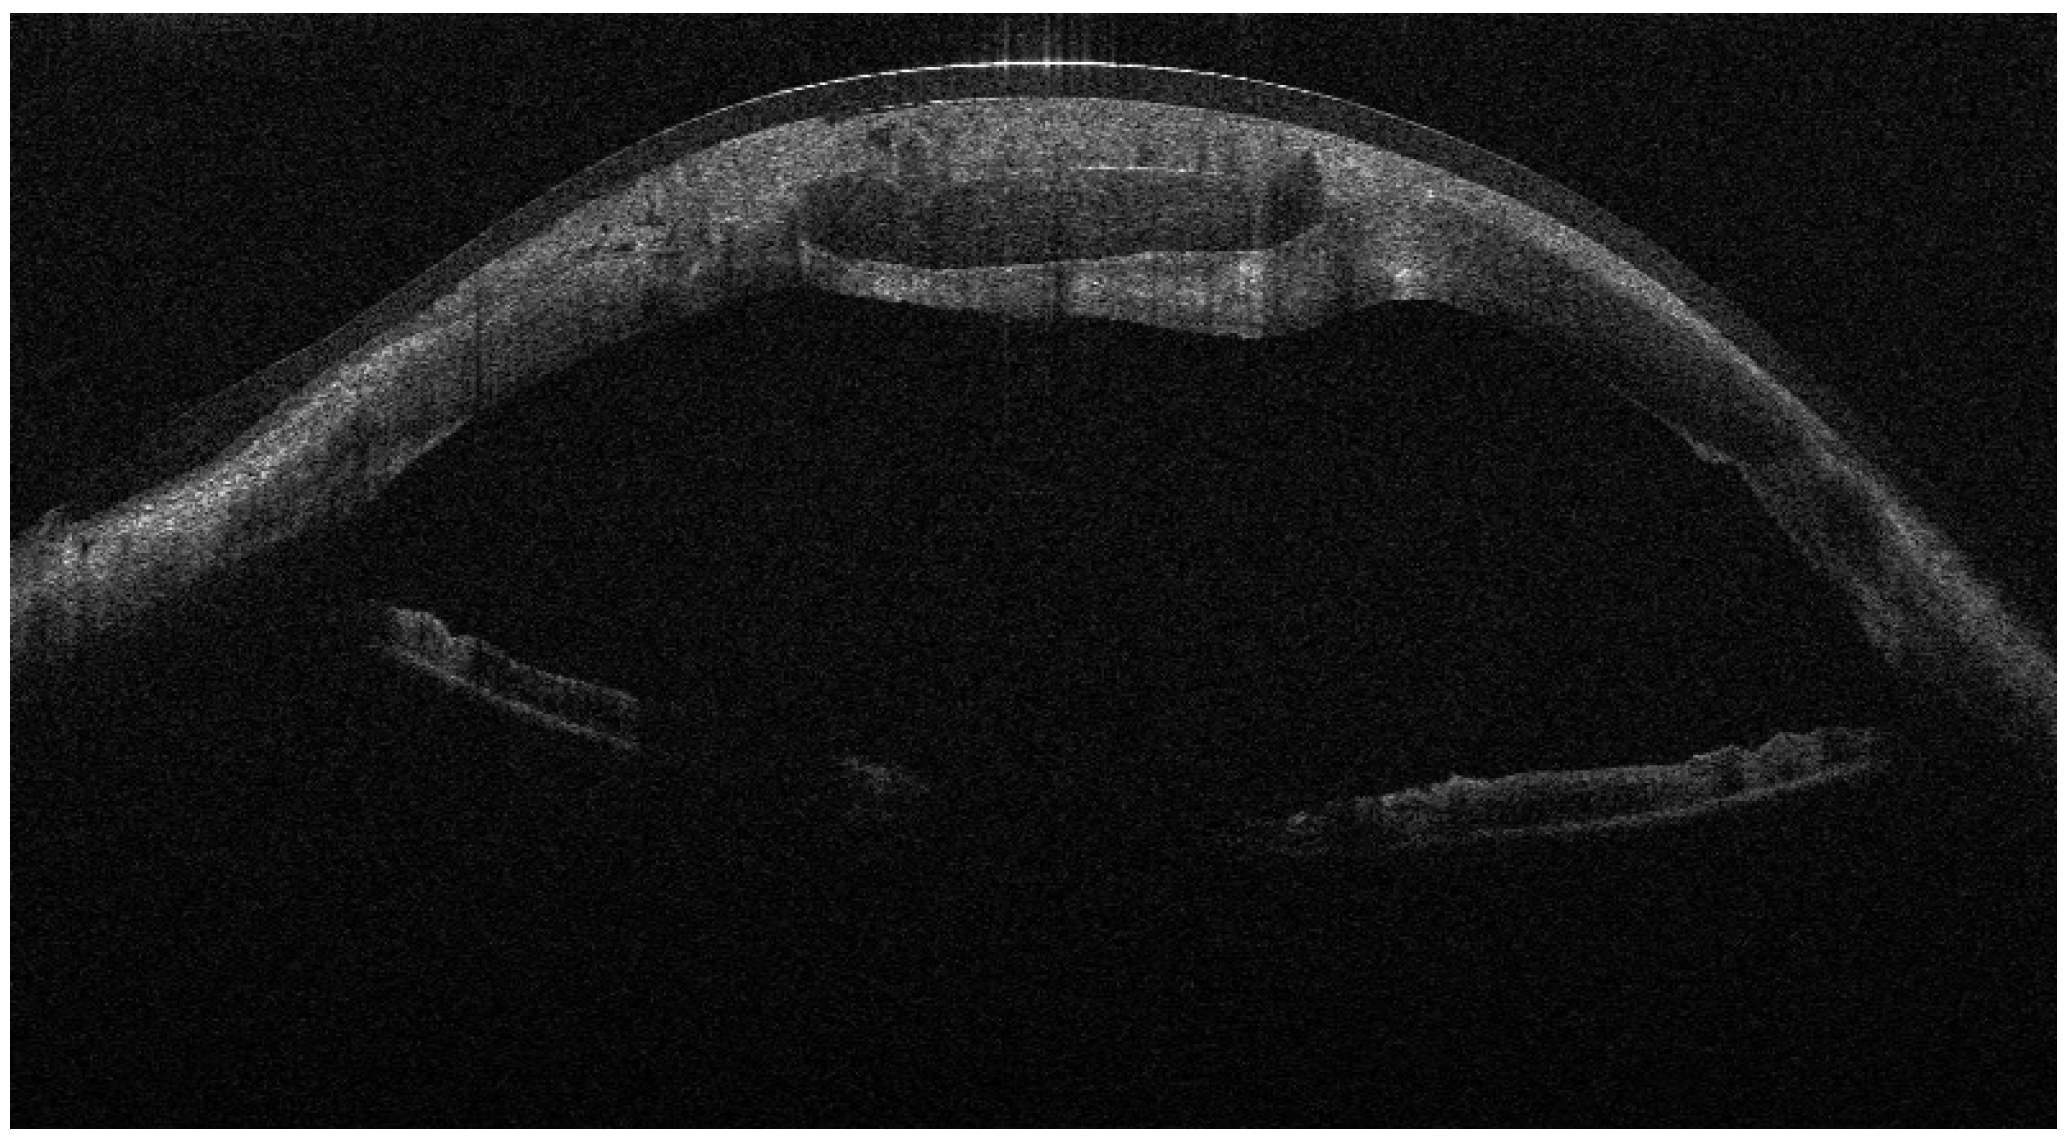

Figure 2. AS-OCT showing the lamellar patch graft centered on the perforation site and covered by the amniotic membrane; the AM appears as a thin hyperreflective layer over the graft surface.

From September 2023 to December 2023, the patient was managed with intensive topical antimicrobial therapy for the corneal abscess, together with aggressive ocular surface support for severe oGVHD-related epithelial instability (preservative-free lubricants, protective bandage contact lens/scleral protection when tolerated, and adjunctive therapies according to the ocular surface status). Despite these measures, progressive stromal melting occurred, culminating in a 4 mm full-thickness perforation in December 2023, prompting urgent tectonic surgery. Standardized preoperative slit-lamp photographs immediately before the urgent repair were not consistently obtainable due to the emergent nature of the procedure and the compromised ocular surface; therefore, urgent repair was performed with a lamellar corneal patch graft wrapped in cryopreserved amniotic membrane (Figure 1 and Figure 2). Cryopreserved human amniotic membrane (AM) was thawed according to the manufacturer’s instructions and rinsed with balanced saline solution. A single AM sheet was prepared to fully envelop the lamellar donor corneal patch. The donor lamellar graft was placed at the center of the AM sheet, which was then folded circumferentially to create a 360° envelope around the graft. The AM was oriented with the stromal side facing the donor corneal tissue and recipient bed, and the basement membrane/epithelial side facing outward, toward the tear film. The AM-wrapped graft was positioned over the corneal perforation and secured with interrupted 10-0 nylon sutures, ensuring complete coverage of the graft–host junction by the AM.